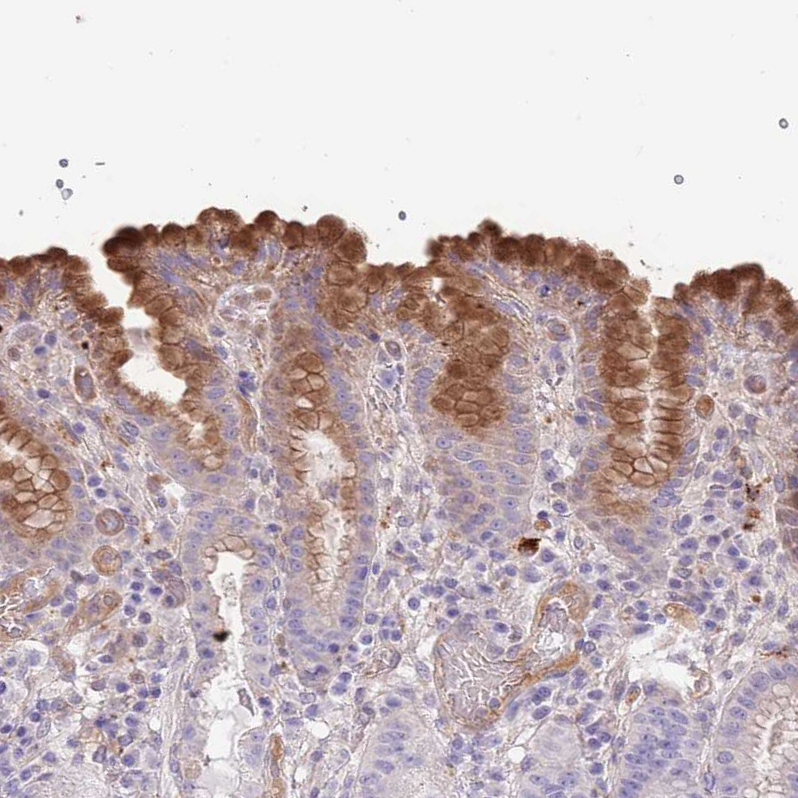

Immunohistochemical staining of human stomach shows moderate cytoplasmic positivity in glandular cells.